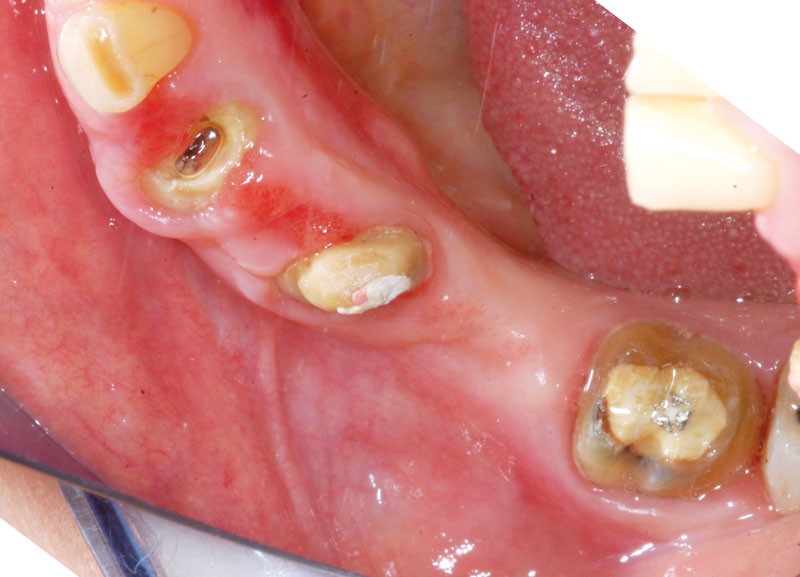

Au maxillaire, 3 implants Astra Tech Implant EV (Dentsply) sont posés en un temps chirurgical. Une empreinte pick-up sera réalisée après 4 mois de cicatrisation.